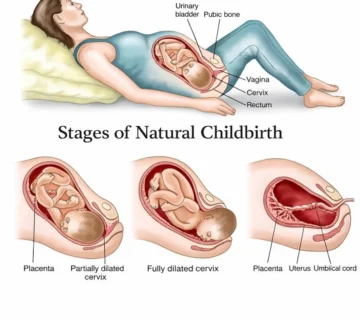

Ҳафтаи 21-уми ҳомиладорӣ яке аз марҳилаҳои ҷолиб ва пурэнергияи давраи модаршавӣ ба ҳисоб меравад. Дар ин вақт ҷанини шумо тақрибан 18–25 сантиметр қад ва тақрибан 390–400 грамм вазн дорад — ба андозаи як банани калон. Ӯ дар дохили моеъи амниотикӣ озодона ҳаракат мекунад, дасту по меандозад ва фазои кофӣ дорад, то ки чарх занад, тебпалезад ва бо қувваи бештар ҷунбад.

Ин ҳафта давраи муҳим барои рушди системаи асаб мебошад: мағзи ҷанин бо суръати баланд инкишоф меёбад, пайвастҳои нави асабӣ пайдо мешаванд ва ҳамоҳангии мушакҳои ӯ беҳтар мегардад. Аз ҳамин сабаб теппазаниҳо ва ҳаракатҳои ҷанин равшантар ва мунтазамтар эҳсос мешаванд. Бисёр модарон дар ин марҳила аввалин бор имконият меёбанд, ки ҷунбиши ҳақиқии ҷанинро эҳсос кунанд ва ҳатто падар метавонад ҳаракатро аз берун ҳис кунад.

Ин марҳила оғози нисфи дуюми ҳомиладорӣ аст — даврае ки ҳам шумо ва ҳам ҷанин ба рушди устувор ва калоншавии босуръат ворид мешавед.

Дар ин ҳафта ҷанин ба нисфи вазни таваллуд мерасад. Ӯ давра ба давра бедор ва хоб мешавад ва ин сабаб мешавад, ки шумо дар як соат чанд маротиба теппазанӣ ҳис кунед.